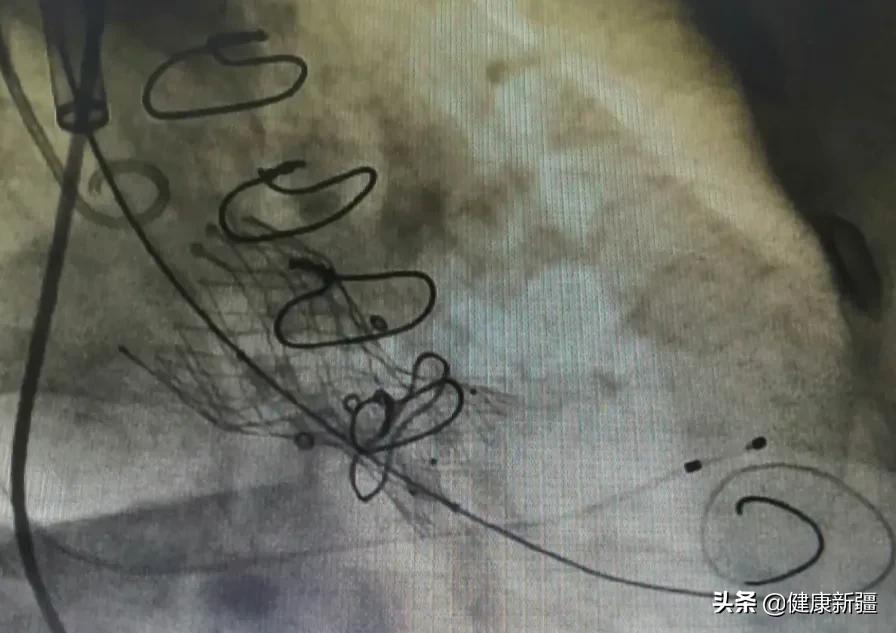

造影下将新的瓣膜输送至主动脉瓣的位置